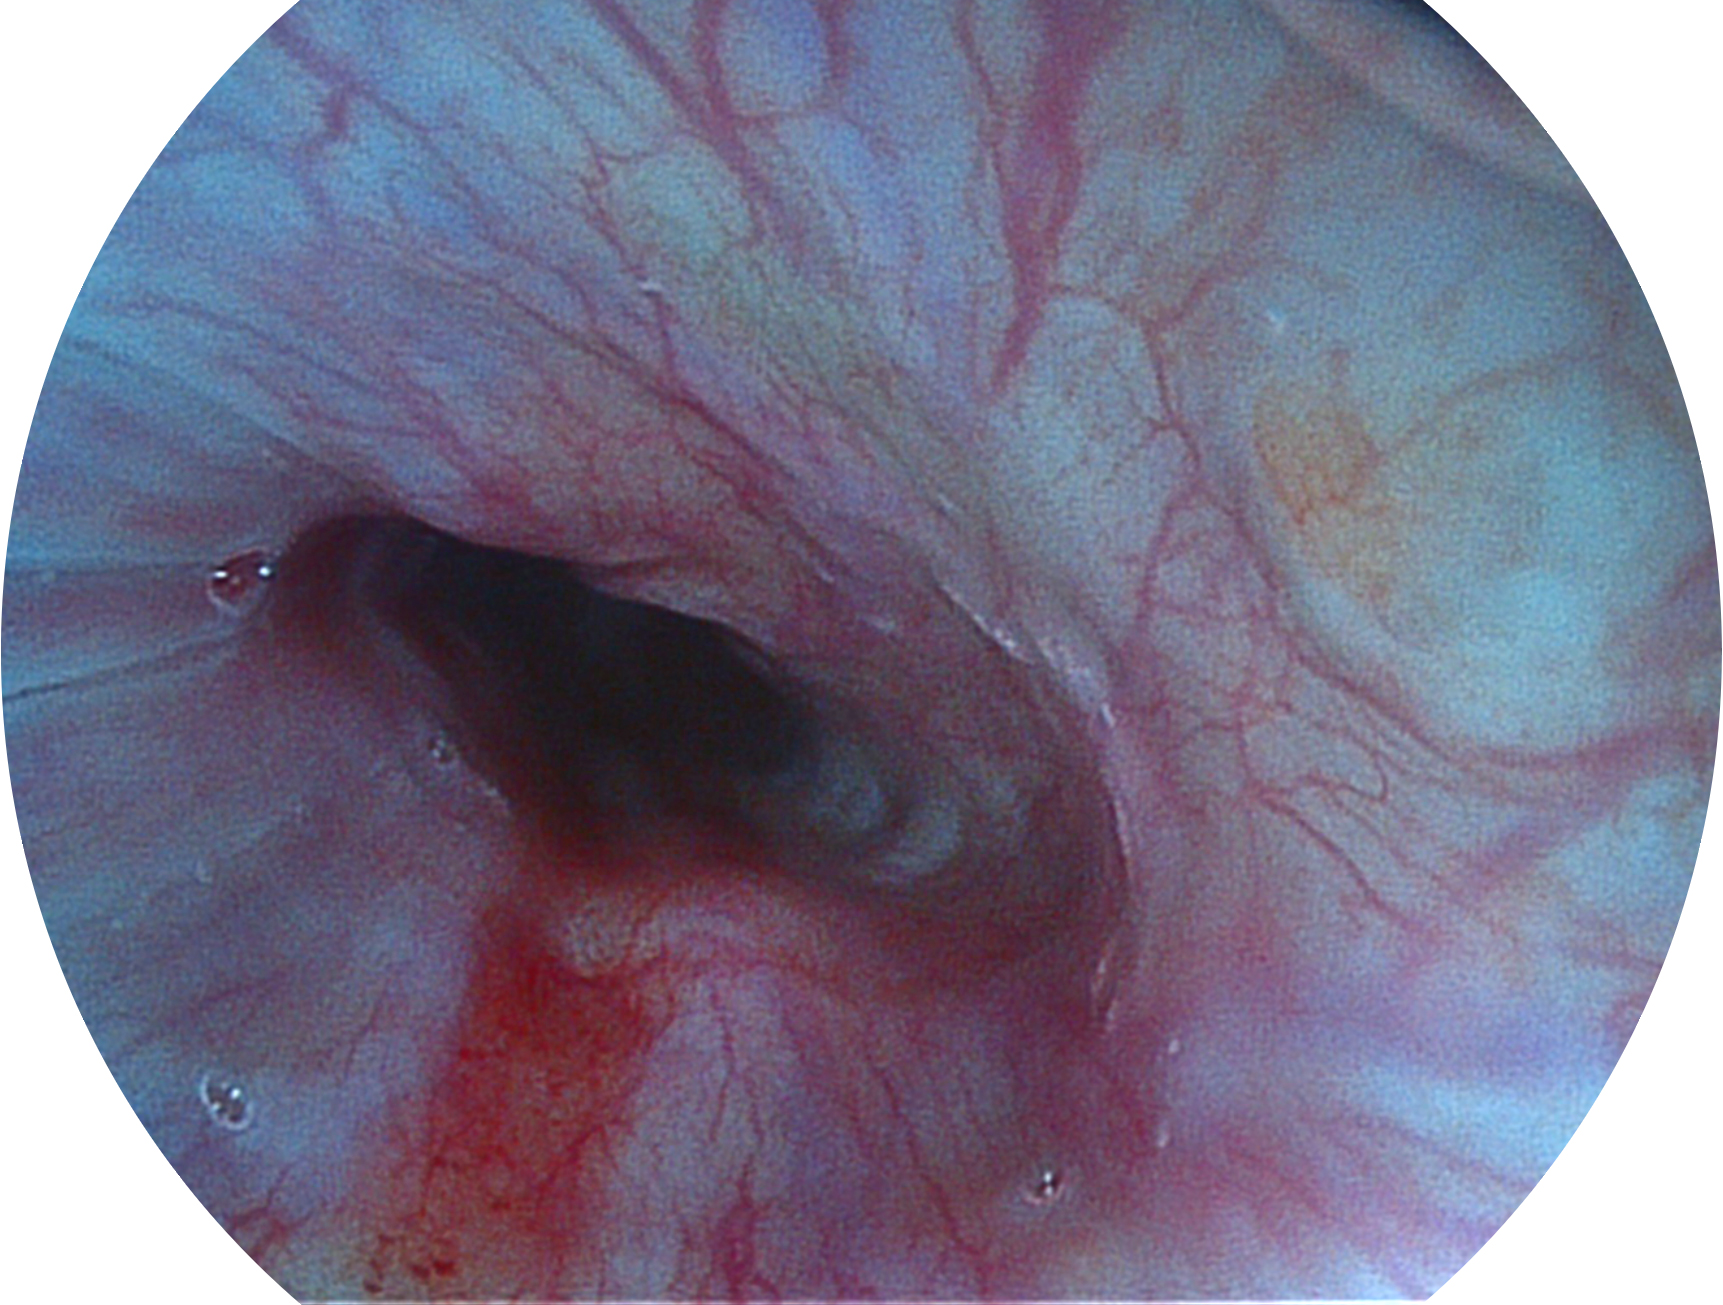

百老汇电子游戏官网新开发的内镜染色技术,主要是基于多波长LED 光源的开发,VLS-55Q 四波长LED 光源是由四个不同颜色的LED光按照相应照明模式所规定的特定发光比例进行合束后形成,合束后形成的照明光的光谱由红光、绿光、蓝光及蓝紫光这四个不同的波段范围构成。具有更高光谱自由度,通过光谱比例的控制,实现了聚谱成像技术,英文全称为“Spectral Focused Imaging, SFI”,缩写为“SFI”和光电复合染色成像技术,英文全称为“Versatile Intelligent Staining Technology, VIST”,缩写为“VIST”。